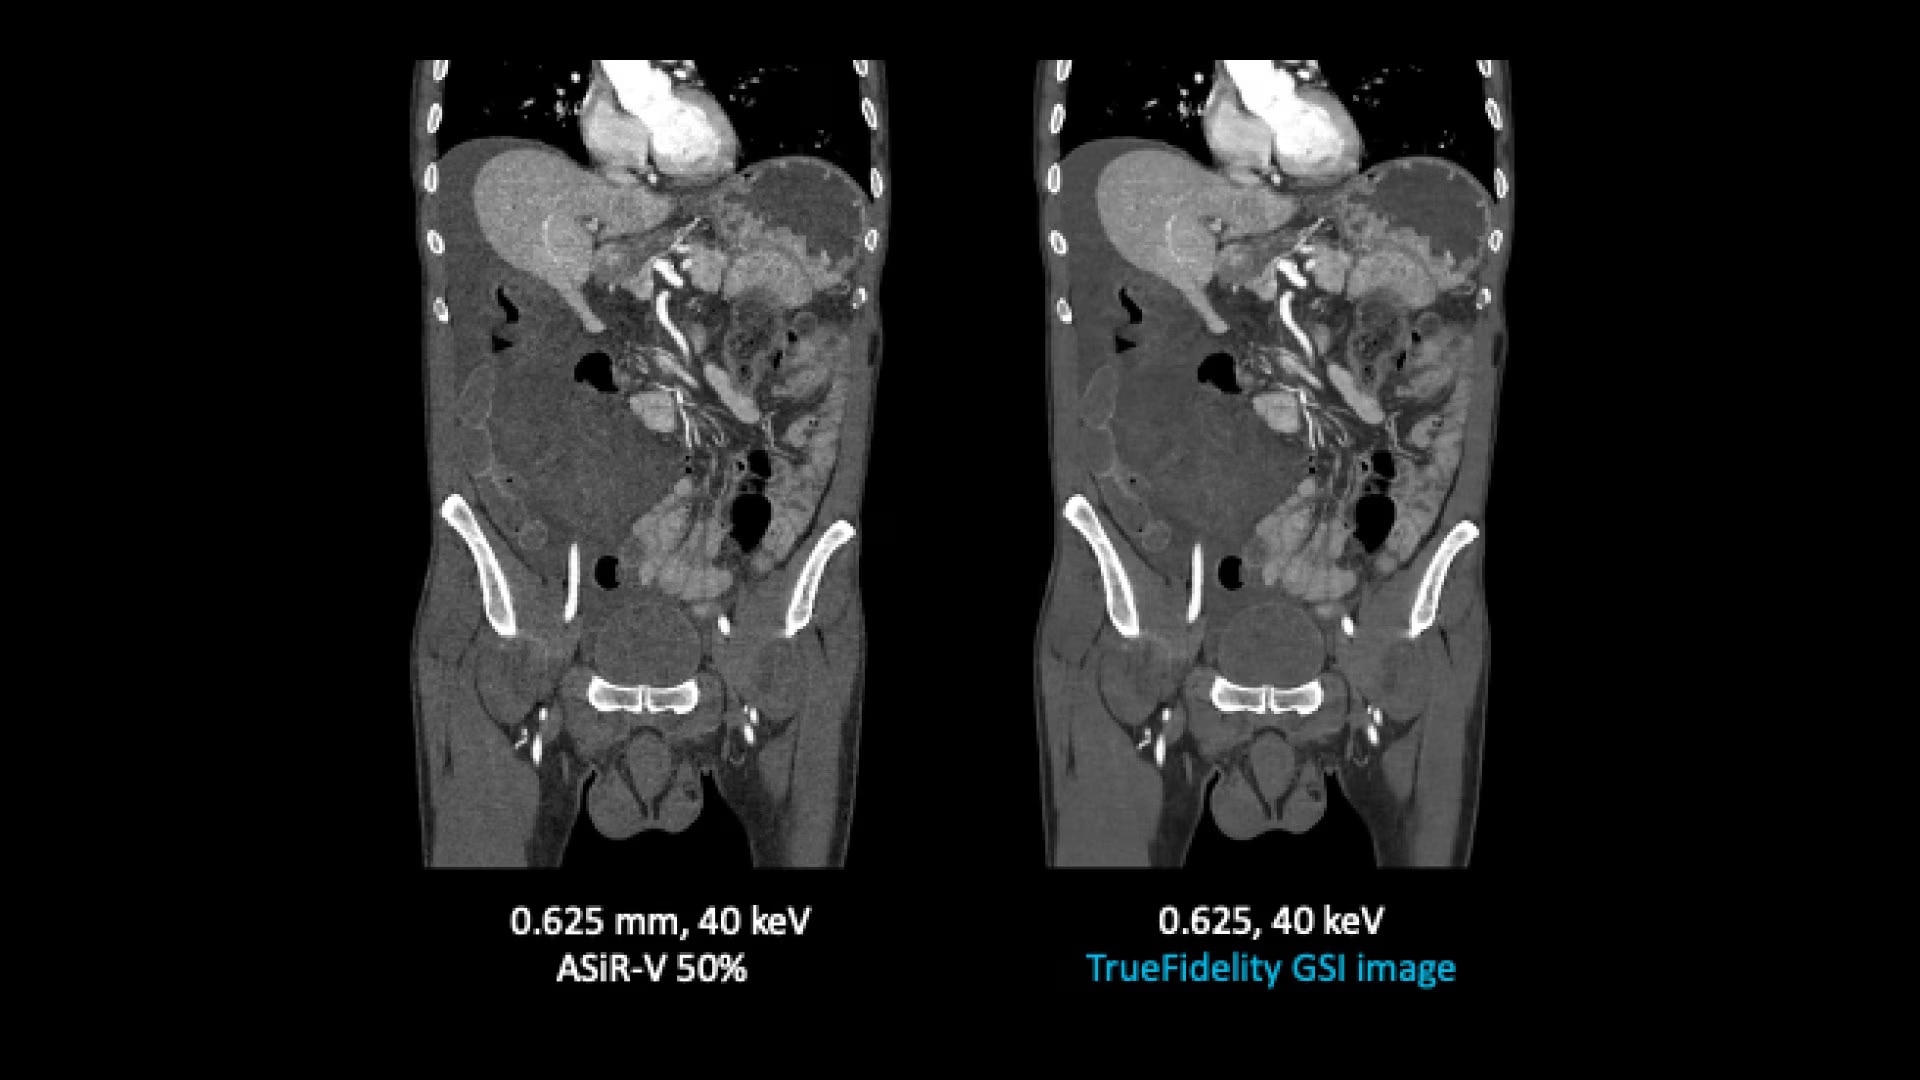

TrueFidelity for GSI now brings the potential to substantially reduce the image noise in all spectral image types

From virtual monochromatic images to material image pairs and virtual non-contrast images, with and without metal artifact reduction. Specifically, reducing the image noise inherent with low keV images resolves one of the traditional technical challenges in adopting more dual-energy protocols across the full patient population.